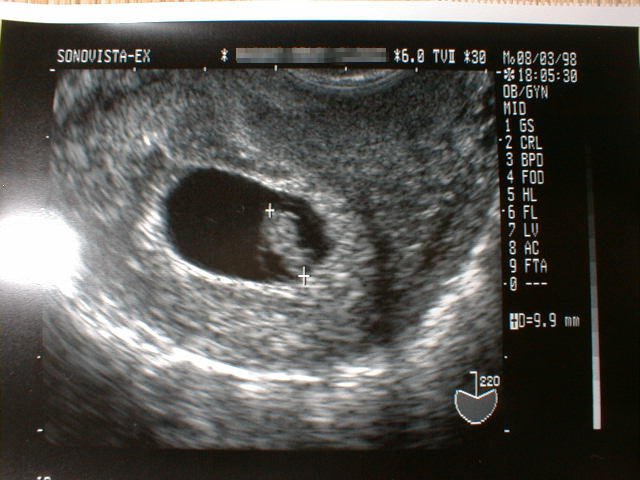

第7週に入った胎児の写真です。

(大きさは、9.9mm)